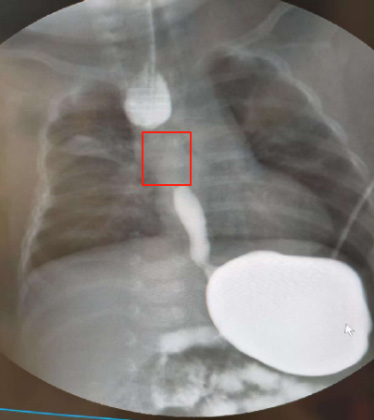

小扎西的食管中间缺失了约4厘米

6月2日,影像检查显示,小扎西的食管终于“养”好了!“他上下食管的重叠段约有1厘米,体重也长到了12斤,基本达到了做食管吻合术的条件。”赵勇说。